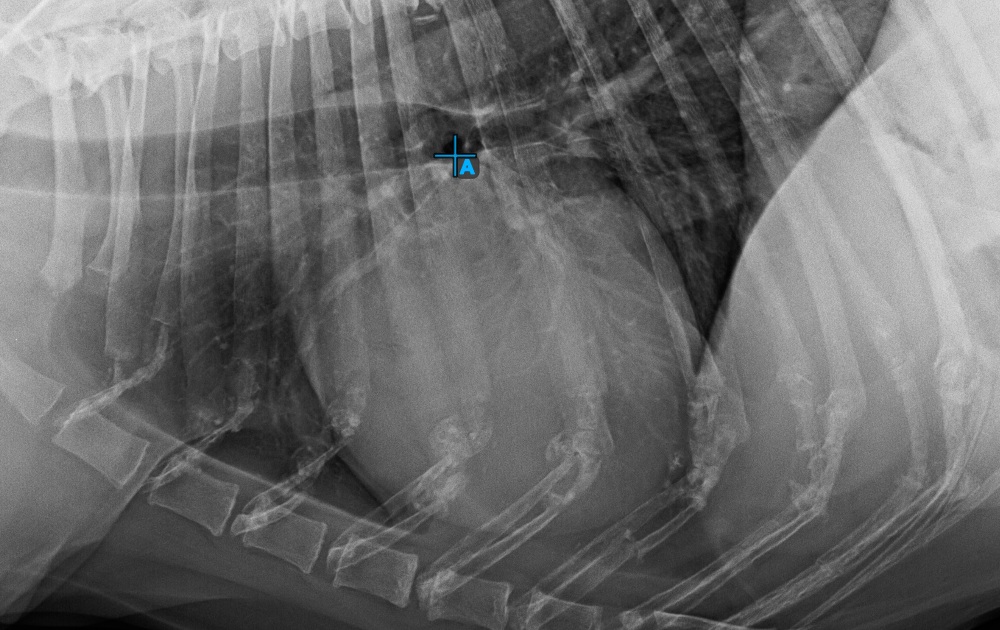

Starten Sie die Messung, indem Sie die Bifurcatio tracheae in der Nähe der Herzspitze markieren.

Das Bild unten zeigt die typische Platzierung des Punkts Bifurcatio tracheae.